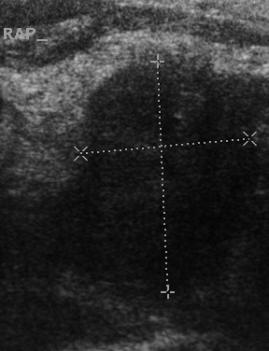

- Tiroid iltihabı (Hashimoto)

- Hashimato'da lazer tedavisi: İlaç dozlarının azaltılması veya kesilmesi ve kilo kontrolü !!!

- Hashimoto hastalığında destek tedavileri